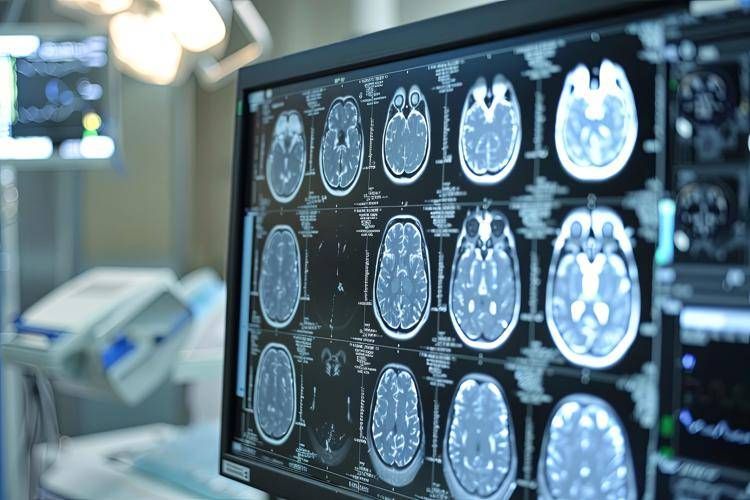

L'ictus rappresenta ancora una sfida di portata globale: ogni anno colpisce circa 12 milioni di persone e nel 20–30% dei casi si tratta di recidive. E' la seconda causa di morte nel mondo e le recidive spesso comportano esiti ancora più gravi rispetto al primo episodio. Nonostante le terapie oggi disponibili, il rischio di un nuovo evento rimane elevato: 1 sopravvissuto su 5 può andare incontro a un secondo ictus entro 5 anni. "Lo studio Oceanic-Stroke - afferma Andrea Zini, direttore della Neurologia e Rete Stroke dell'Irccs Istituto delle scienze neurologiche dell'ospedale Maggiore di Bologna - segna un cambiamento importante nella ricerca neurologica. Gli inibitori del Fattore XIa come asundexian rappresentano una nuova frontiera nella prevenzione dell'ictus, un passo significativo nella lotta contro le recidive, soprattutto per i pazienti con ictus ischemico non cardioembolico per i quali le opzioni terapeutiche non sono state sostanzialmente innovate negli ultimi anni. Asundexian, primo farmaco di questa classe a completare con successo uno studio di fase 3, potrebbe offrire una soluzione efficace per ridurre il rischio di ictus ricorrenti in questa popolazione. La terapia antiaggregante attualmente in uso non è sufficiente per prevenire completamente i secondi ictus, il che rende l'approvazione di nuovi trattamenti ancora più cruciale"

Asundexian ha ottenuto la designazione fast track dalla Food and Drug Administration degli Stati Uniti come potenziale trattamento per la prevenzione dell'ictus nei pazienti con ictus ischemico non cardioembolico, ricorda la nota. Tuttavia - si legge - va sottolineato che asundexian è ancora un farmaco sperimentale e non è stato ancora approvato da alcuna autorità sanitaria. Lo studio Oceanic-Stroke ha analizzato efficacia e sicurezza di asundexian, inibitore orale del Fattore XIa, somministrato alla dose di 50 mg una volta al giorno, per la prevenzione dell'ictus ischemico in pazienti che avevano recentemente avuto un ictus ischemico non cardioembolico o un attacco ischemico transitorio (Tia) ad alto rischio. Il trattamento è stato valutato in combinazione con la terapia antipiastrinica standard. Si tratta di uno studio multicentrico e internazionale, randomizzato, controllato con placebo, in doppio cieco, a gruppi paralleli e guidato dal numero di eventi, che ha arruolato oltre 12.300 pazienti.